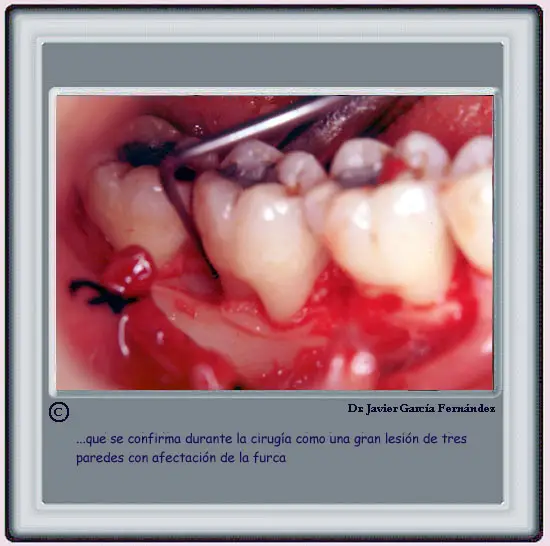

image220